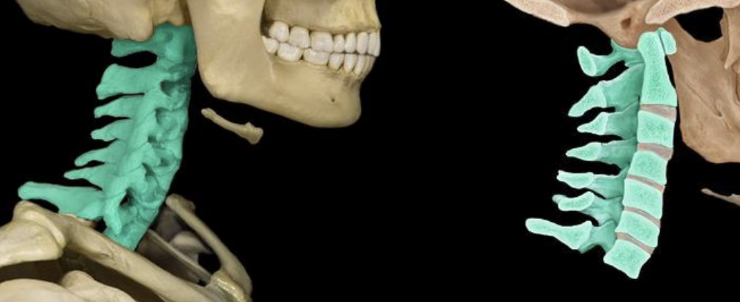

cervical (7) vertebrae

<p></p>

atlas (C1)

knowt flashcard image

axis (C2)

dens (odontoid process)

transverse foramen